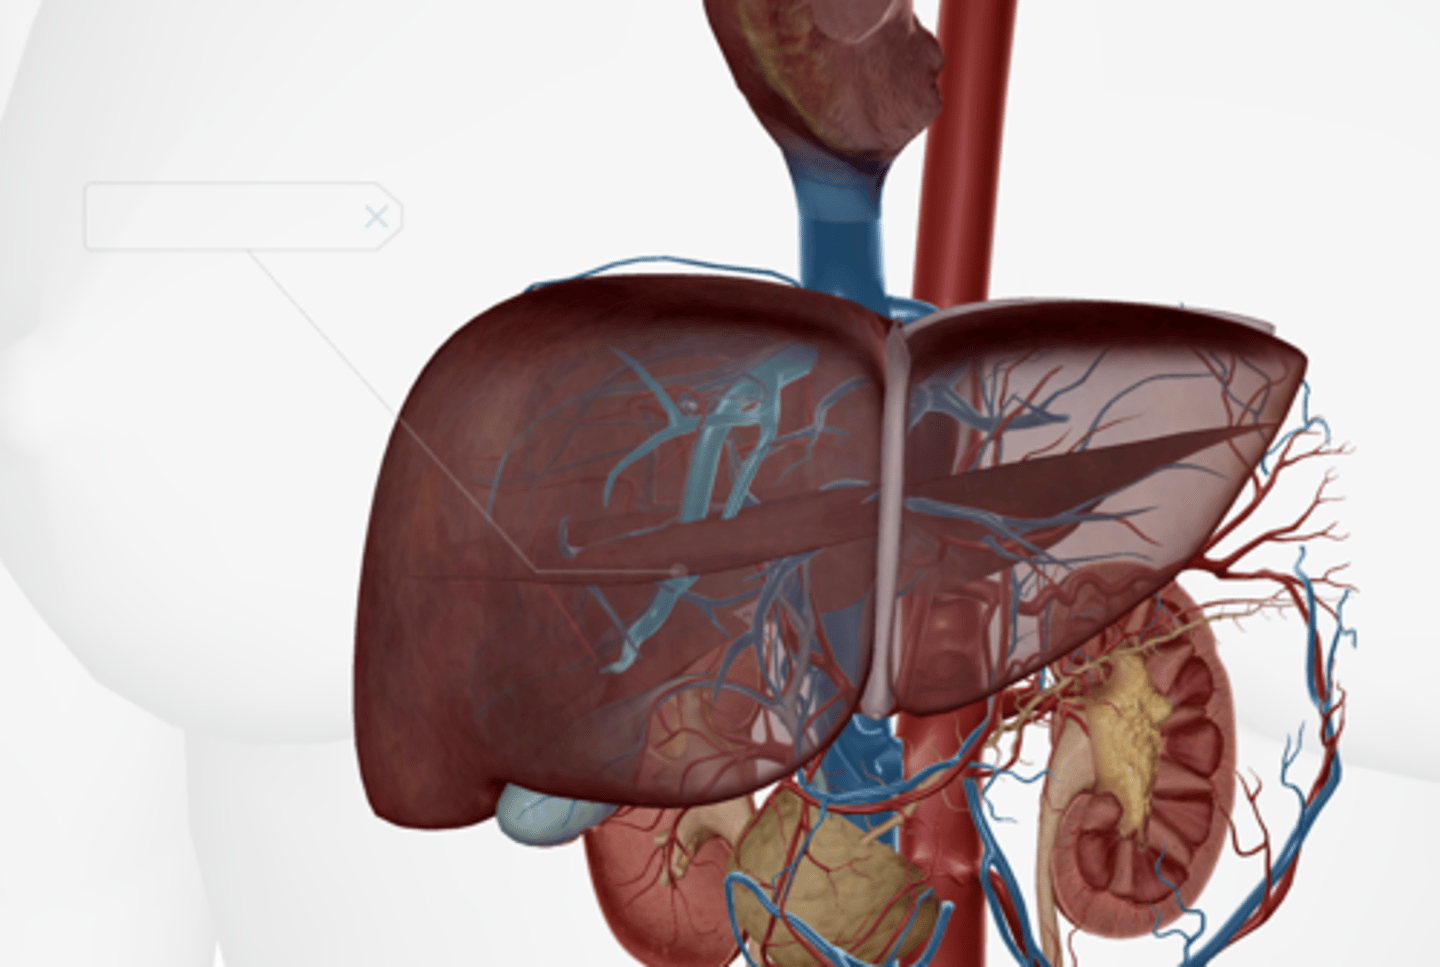

Liver

Hepatic artery & vein

Falciform ligament